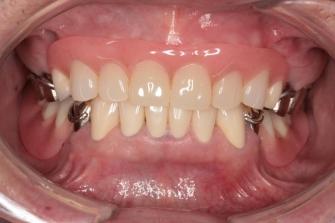

◎右写真 治療終了

週に二回来院、約1年で治療終了

すべて保険内治療です。

最初は歯周病治療を行い、その後1本1本虫歯の治療、

そしてここが一番のポイント!

咬み合わせがずれてしまっているので

仮歯、仮の入れ歯を入れながら噛み合わせを整えていきます。

噛めるようになった、入れ歯は合わないものだと思っていたが

これなら食べられる!と喜んでいらっしゃいました。